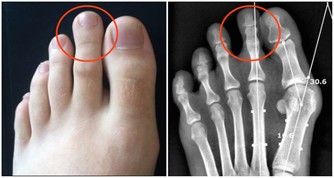

關節軟骨大概有1到2毫米,作用就是緩沖壓力,保護骨骼不破裂。

它就相當於跑道上的橡膠,能夠幫助大家緩衝上下運動時的一個力,進而來保護自己的關節。